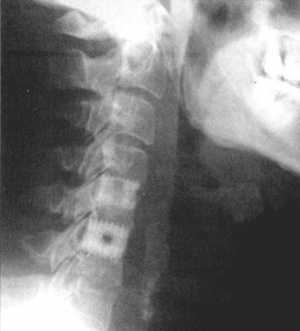

Рис. 3.5: а - травматический вывих С5-С6 позвонков;

б - межтеловая стабилизации металлическим цилиндром сразу после операции;

в - через 3 года после операции. |